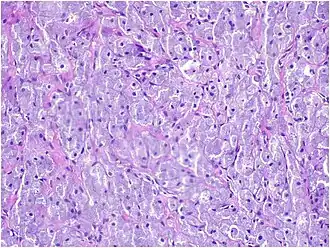

Histopathological Characteristics

Histopathologically, congenital epulis is usually characterized by the presence of big, rounded cells that fill the mucosa's lamina propria and have round to oval nuclei and an abundance of eosinophilic cytoplasm.[10] A thin layer of connective tissue separated the surface layer of cells from the growing new cells. Numerous histological traits, such as a fibrous and granulomatous appearance, have been reported in recent research.[10]

Microscopically, congenital epulis is composed of:

- Sheets of proliferating polygonal to round cells with overlying thin squamous, eosinophilic, granular cytoplasm[12][13]

- Centrally located, round nuclei [7]

These histopathological features are essential in distinguishing congenital epulis from other gingival and soft tissue neoplasms.